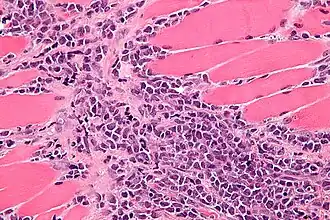

![]() Микрофотография миелоидной саркомы в ткани мышцы | |